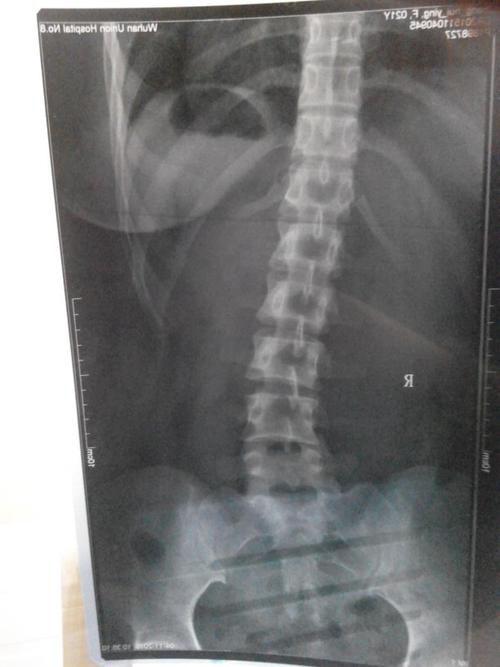

腰椎向左侧弯示意图

腰椎向左侧弯示意图,腰椎向左侧弯锻炼图

请问这是脊椎向左弯还是向右弯,,这个是腰椎放射x线.

我院腰椎正侧位及动力位x片显示,患者腰椎呈姿势性侧弯,退变明显,l4/5

髋关节活动受限,只能靠腰椎弯曲代偿